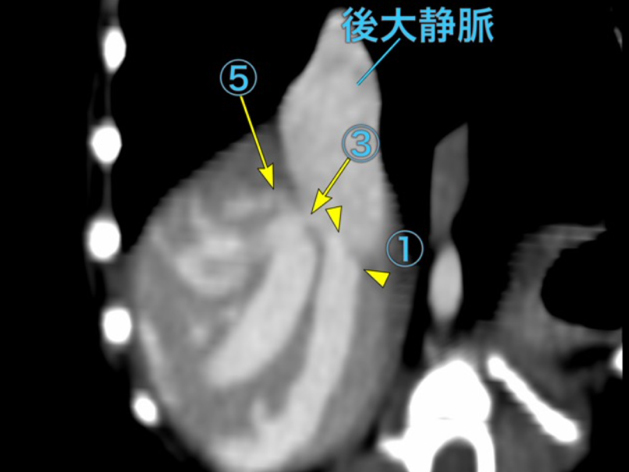

肝内門脈シャントの精査を目的にCT検査を実施しました。検査の結果、右外側肝葉において肝内門脈から体循環へのシャントが確認され、後大静脈へ流入する血管が約5本(うち1本は太く、残りの4本は細い)存在することが判明しました。 また、右外側肝葉への血流が非常に豊富である一方、他の肝葉への門脈血流は細いことが確認されました。そのため、右外側肝葉切除を行った場合には術後に門脈圧亢進を生じる可能性が高いと判断されました。 これらの所見を踏まえ、段階的な肝内門脈シャント閉鎖を目的とした血管プラグ塞栓術を希望され、施術する運びとなりました。

手術前のCT検査での評価